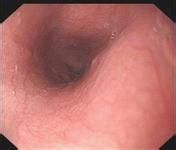

萎缩性胃炎是由于胃黏膜受到反复损伤,导致固有腺体萎缩或消失而形成,对人体的危害非常严重,如果不及时治疗,很可能并发胃溃疡、出血,甚至恶化成癌。